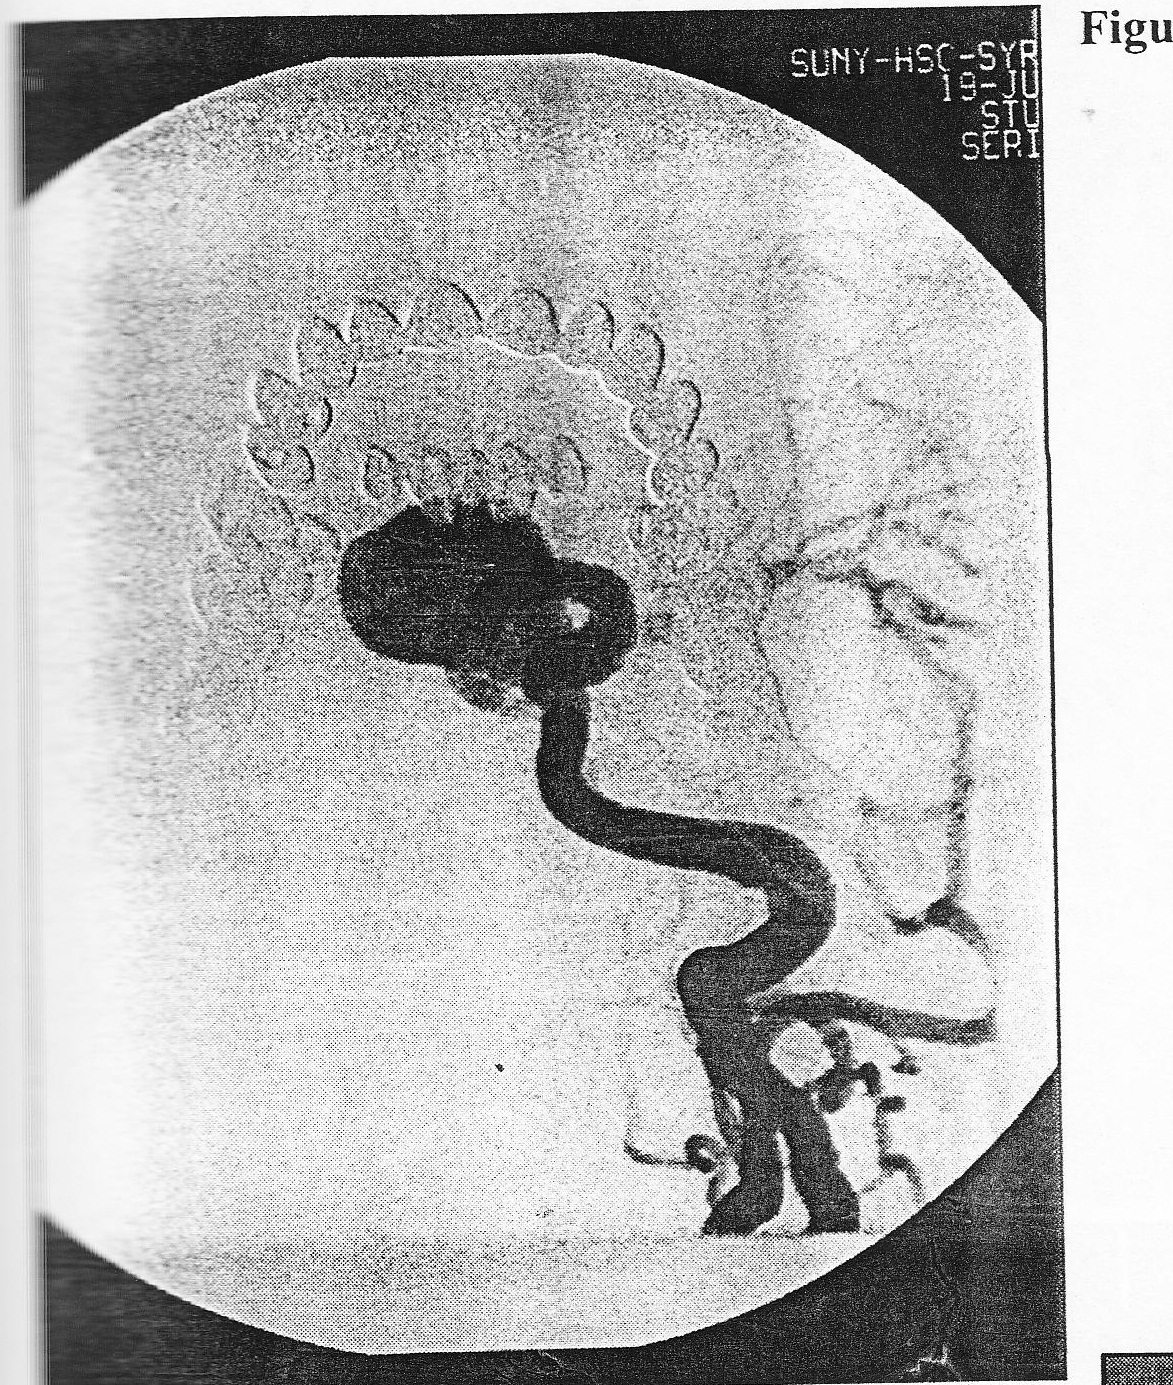

A 40-year-old woman presented to the emergency room with the worst headache of her life. A CT of the head demonstrated diffuse subarachnoid hemorrhage and angiography revealed a middle cerebral artery aneurysm. The patient underwent a pterional craniotomy and clipping of the aneurysm. Postoperativelly, she did well until day 3, when she developed hemiparesis and bilateral carotid distribution vasospasm confirmed by angiography. She was treated with hypertensive hypervolemic therapy. A second angiogram perfomed one week later is pictured in Figure 27. Based upon clinical and angigraphy findings, which of the following statements is FALSE?

A 40-year-old woman presented to the emergency room with the worst headache of her life. A CT of the head demonstrated diffuse subarachnoid hemorrhage and angiography revealed a middle cerebral artery aneurysm. The patient underwent a pterional craniotomy and clipping of the aneurysm. Postoperativelly, she did well until day 3, when she developed hemiparesis and bilateral carotid distribution vasospasm confirmed by angiography. She was treated with hypertensive hypervolemic therapy. A second angiogram perfomed one week later is pictured in Figure 27. 100. which of the following statements about the vertebral angiogram (Figure 28) of the same patient is FALSE?

A. This disease process rarely involves the posterior circulation.

B. In this angiogram, the basilar artery is affected by the disease process.

C. Posterior circulation aneurysms have been reported in association with this disease.

D. the carotid arteries are affected bilateral almost 60% of the time.

E. When the posterior circulation is affected by this disease, the anterior circulation is almost always affected.

When treating the aneurysm pictured in Figure 29, which of the following statements is FALSE concerning the use electrically detachable coils as primary therapy?

A. bulging of the coils through the neck of the aneurysm can result in parent artery occlusion.

B. Coil placement may cause mechanical rupture of the aneurysm.

C. Vasospasm can result from catheter placement.

D. Once coils are placed, craniotomy for surgical ligation of the neck is no longer possible.

E. Delayed aneurysmal rupture can occur following the procedure